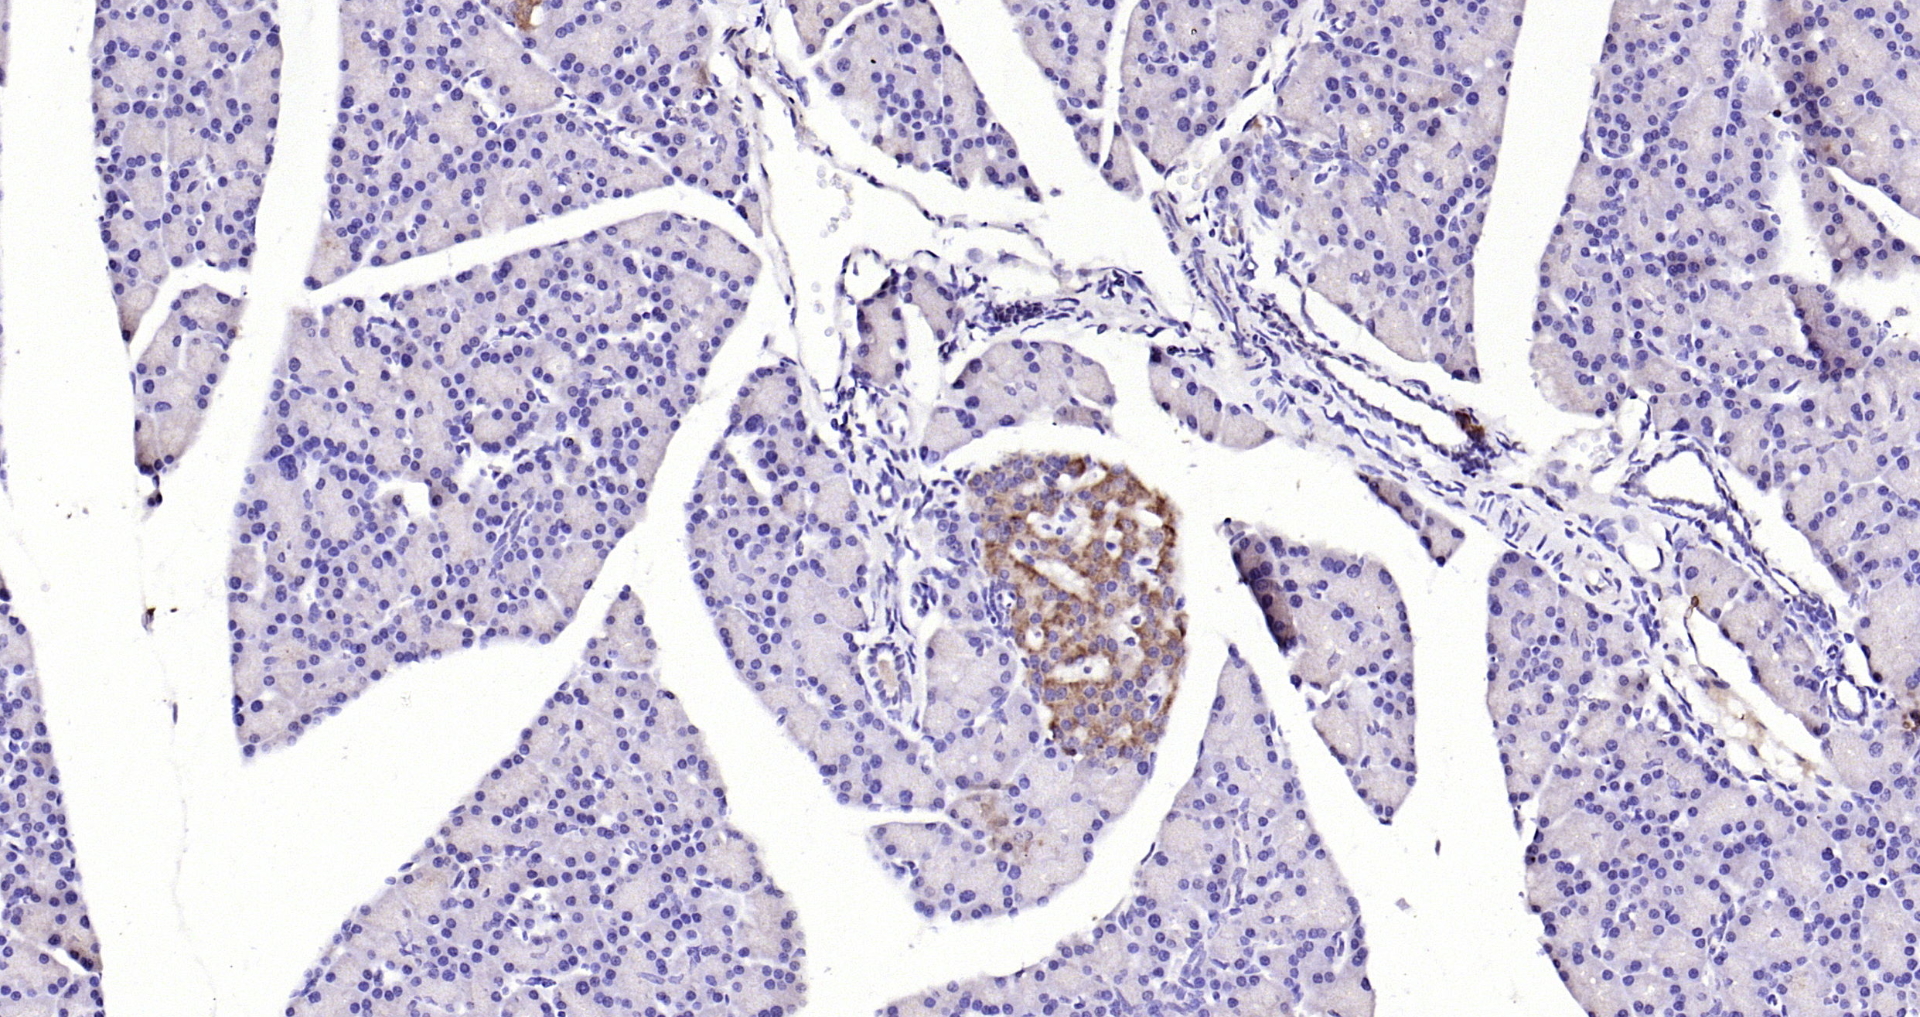

GPR49/LGR5 Polyclonal Antibody

• IHC-P

Catalog # bs-20746R

Product Name GPR49/LGR5 Polyclonal Antibody

IHC-P 1:200-400